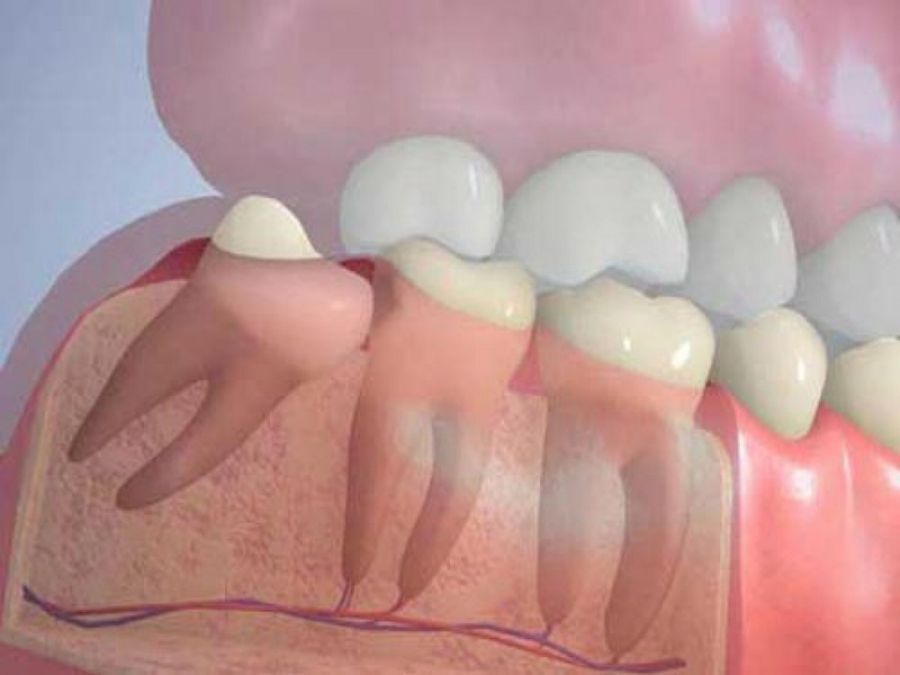

Yirmi yaş dişleri olarakta bilinen üçüncü azı dişleri sıklıkla kemik içerisinde gömülü kalabilir ya da yanlış bir pozisyonda sürebilir. Bu durumda cerrahi yöntemlerle lokal anestezi altında çekilmeleri gerekmektedir. Bazen gömülü kalmış köpek dişlerine de aynı tip cerrahi işlemler uygulanabilir.